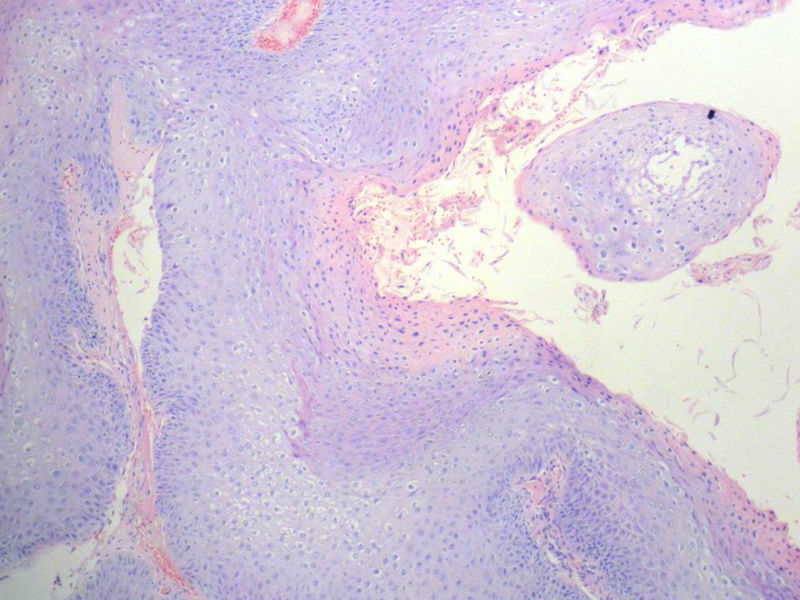

男,72岁,右耳听力下降两个月,检查右外耳道有黄豆大肿物,表面乳头状,手术切除。

乳头状瘤

乳头状瘤,有轻度异形,有恶变倾向

乳头状瘤,轻度异形,有恶变倾向

乳头状瘤,上皮内可见挖空样细胞,建议HPV检测

鳞状上皮乳头状瘤,未发现恶性变。